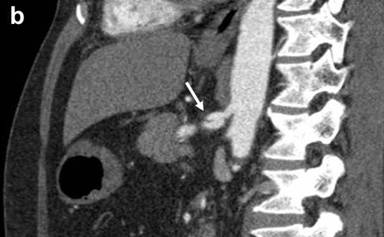

Bleeding from the papilla of Vater was not evident with upper gastrointestinal endoscopy on the day of admission. Conservative treatment was performed for the acute pancreatitis because the patient was hemodynamically stable. The epigastric pain and the serum amylase level improved after conservative treatment. During hospitalization, however, the patient developed the same epigastric pain as that usually experienced before melena, and the serum amylase level was found to be 243 U/L. We performed emergency upper gastrointestinal endoscopy to confirm the diagnosis of hemosuccus pancreaticus. Bloody pancreatic juice was observed exuding from the papilla of Vater (Figure 2). We concluded that the recurrent episodes of epigastric pain and melena had been caused by hemosuccus pancreaticus. There were no clinical or laboratory findings suggestive of arteriosclerosis or vasculitis, and diagnostic imaging showed no evidence of chronic pancreatitis or pancreatic pseudocyst. We therefore considered that the splenic aneurysm was due to segmental arterial mediolysis. We planned transcatheter arterial coil embolization for the splenic aneurysm, and the patient was discharged. However, he was re-admitted before the scheduled embolization because of sudden epigastric pain and, when tested, his serum amylase level was found to be 631 U/L. CECT revealed leakage of contrast medium into the main pancreatic duct from the aneurysm, along with dilatation of the upstream main pancreatic duct (Figure 3ab).

Figure 2. Upper gastrointestinal endoscopy revealing bloody pancreatic juice from the papilla of Vater. |